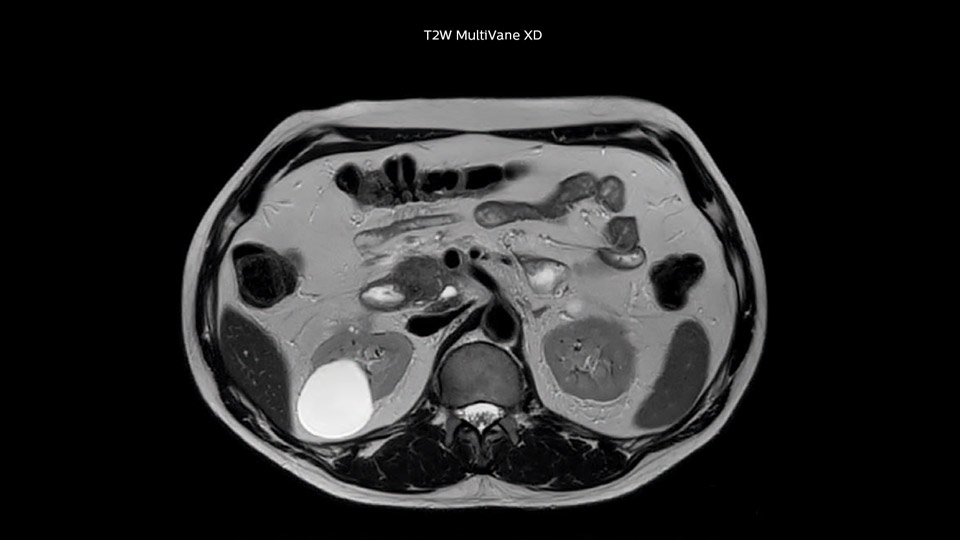

Dr. Baumann then implemented MultiVane XD for motion correction. It uses an extended reconstruction algorithm for imaging that is virtually motion free. “With MultiVane XD we get excellent motion-corrected images with high spatial resolution. We typically first optimize our scan for high image quality, and when satisfied with that, we try to reduce the scan time. So, we combined MultiVane XD with dS SENSE, which allows us to shorten the scan time,” he explains. “The performance of MultiVane XD in liver imaging is outstanding. MultiVane XD with dS SENSE is a powerful development in improving liver image quality.” “As we use breathhold imaging for T2-weighted liver scans, we depend on the patient’s ability to cooperate with the exam. This can present a real challenge when we are looking for small lesions, such as in our oncological patients. However, with MultiVane XD motion correction, we get excellent images. This is important for our surgeons, because they want to know exactly where the lesions are.”

“Our liver exams are quite fast,” says Dr. Baumann. “If the patient tolerates it, we use an arms-up position to reduce the FOV and speed up the exam with dS SENSE.” “We acquire one transversal high resolution T2-weighted sequence with 3 mm slice thickness, for example for pancreas or liver lesions. Then we also add a T2 fat suppressed MultiVane XD SPIR sequence. We perform these two routinely in our liver imaging. We use high dS SENSE factors to significantly shorten scan times to 2-4 minutes, which can improve our protocol; it’s a very robust scan.” “We include mDIXON for the dynamic sequences because of the robust and homogeneous fat suppression we get with that. We had been using eTHRIVE, but we are now quite happy with mDIXON. Sometimes we use a medication to calm the bowels, to further improve the image quality.”